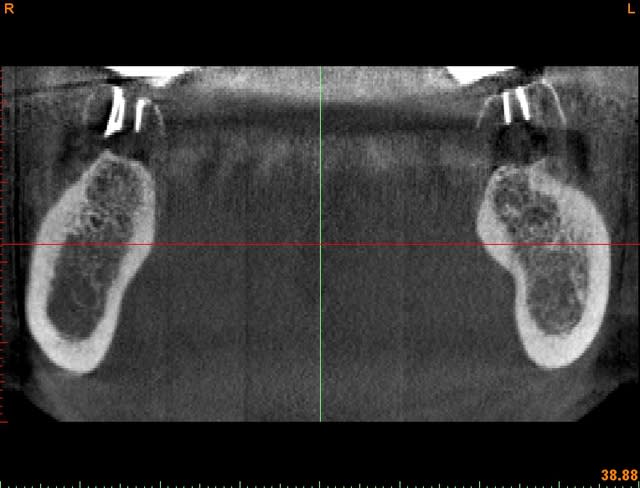

c'est d'avantage que la simple face vestibulaire en fait, c'est la dent en entier!

je fais ce choix parce que j'utilise un logiciel de planification implantaire et que j'essaie de connaitre le meilleur axe possible avant l'implantation et qui puisse respecter le couloir prothétique.

si on utilise uniquement un forage avec un peu de gutta, rien d'autre ne sera visible au scan que ton cône, tu perds donc pas mal d'informations.

toutefois, tu peux utiliser un cône de gutta (ou un guide de forage en titane comme ici) en recouvrant ta dent avec un mélange de ZnO-eugenol (mélange cortisomol par exemple) que tu appliques directement au pinceaux.

tu laisses sécher un peu et le tour est joué.

au scan tu peux voir si ton axe et bon (technique à postériori) et la trace de ta dent.

exemple: photo ci-jointe